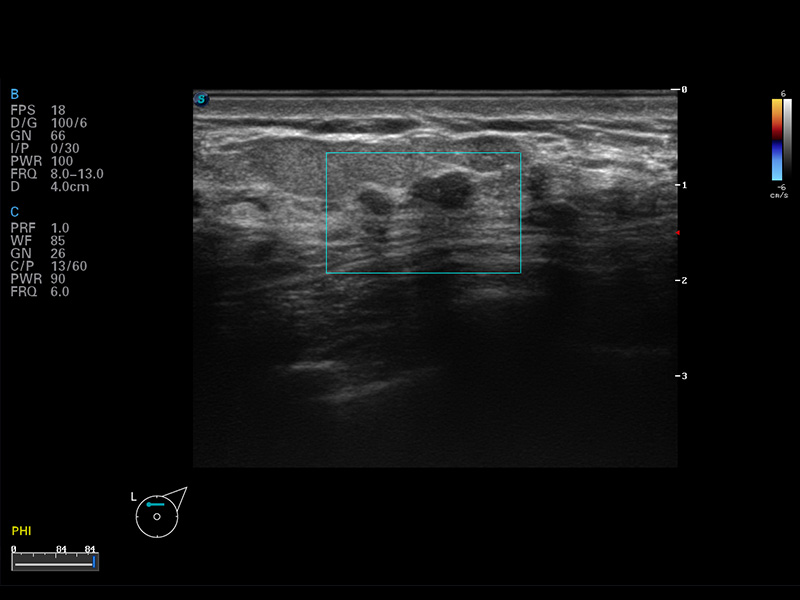

S8 EXP便携式彩色多普勒超声诊断仪是狗万官方网站研发的高端全身应用型便携彩超。高通道的VIS平台融合可视化(Visual)、智能化(Intelligent)和人性化(Smart)的特点,配以狗万官方网站自主研发生产的探头大家族,使您能够快速、准确的获得病人信息,提高工作效率的同时减轻疲劳。

谐波成像